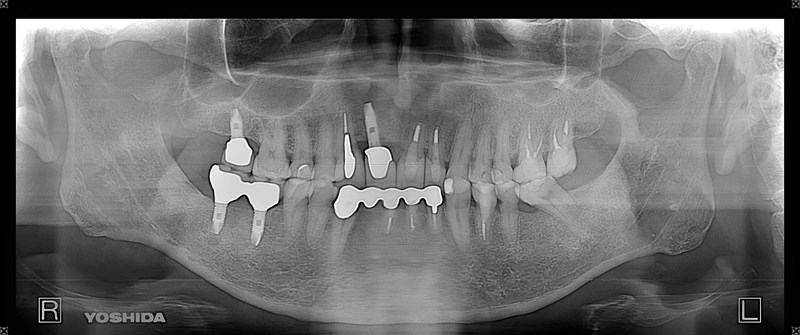

症例240代 女性 主訴 義歯が動いて煩わしい

治療前

治療後

入れ歯だと奥歯しっかり噛めず、取り外しも煩わしいので固定制のインプラントにして欲しいと訴え来院。

左右大臼歯部は、残存骨が1~2㎜程度で骨高が不足している為、ソケットリフト(上顎洞洞底膜挙上術)を行い、インプラントを埋入。口腔内全体で7本のインプラントを埋入。

約4ヶ月の治療期間を経て、全てジルコニアを装着し終了。

リスクとしては外科的侵襲がある。デメリットは、保険外診療の為、経済的負担がある。

費用 381万(税込)(オペ・仮歯・最終補綴物まで含む)